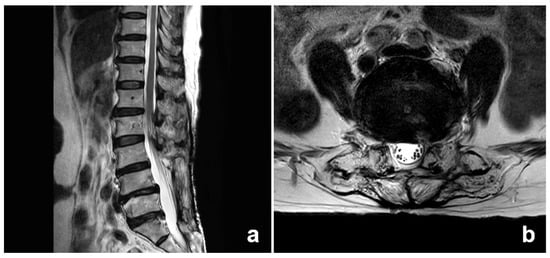

A 69-year-old woman (162 cm in height, 52 kg in weight) sought medical attention at our hospital, citing LBP that had worsened over a span of 3 years. The patient complained of discomfort during lumbar flexion and extension, with the pain localized to the left side of the dorsal region, although episodes of radiating pain occasionally extended to the ipsilateral posterior thigh. Importantly, no neurological impairments were apparent. Her subjective assessment, quantified using the visual analog scale (VAS), yielded a pain intensity of 7 out of 10. Notably, the patient underwent posterior lumbar interbody fusion at the L3–5 vertebrae 6 years prior, a historical intervention for lumbar spondylolisthesis. Postoperative outcomes proved unsatisfactory, prompting a second surgery for metallic implant removal 3 years prior to the current presentation. In spite of the previous two surgical procedures, she continued to experience enduring, severe localized pain in the lower left back, situated to the side of the midline and radiating outward without any accompanying radicular symptoms. Imaging studies, including magnetic resonance imaging (MRI), revealed no neurological abnormalities (Figure 1), and there were no other conditions requiring surgical interventions.

Figure 1.

Magnetic resonance (MR) images obtained from the patient. (a) Sagittal and (b) Axial images show that the metal fixations at the L4/5 level are completely removed by the previous surgery and there are also not any neurological abnormalities.